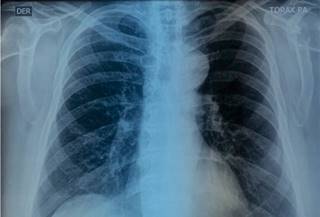

Se solicitó una placa de tórax, que mostró prominencia del botón aórtico (Figura 1).